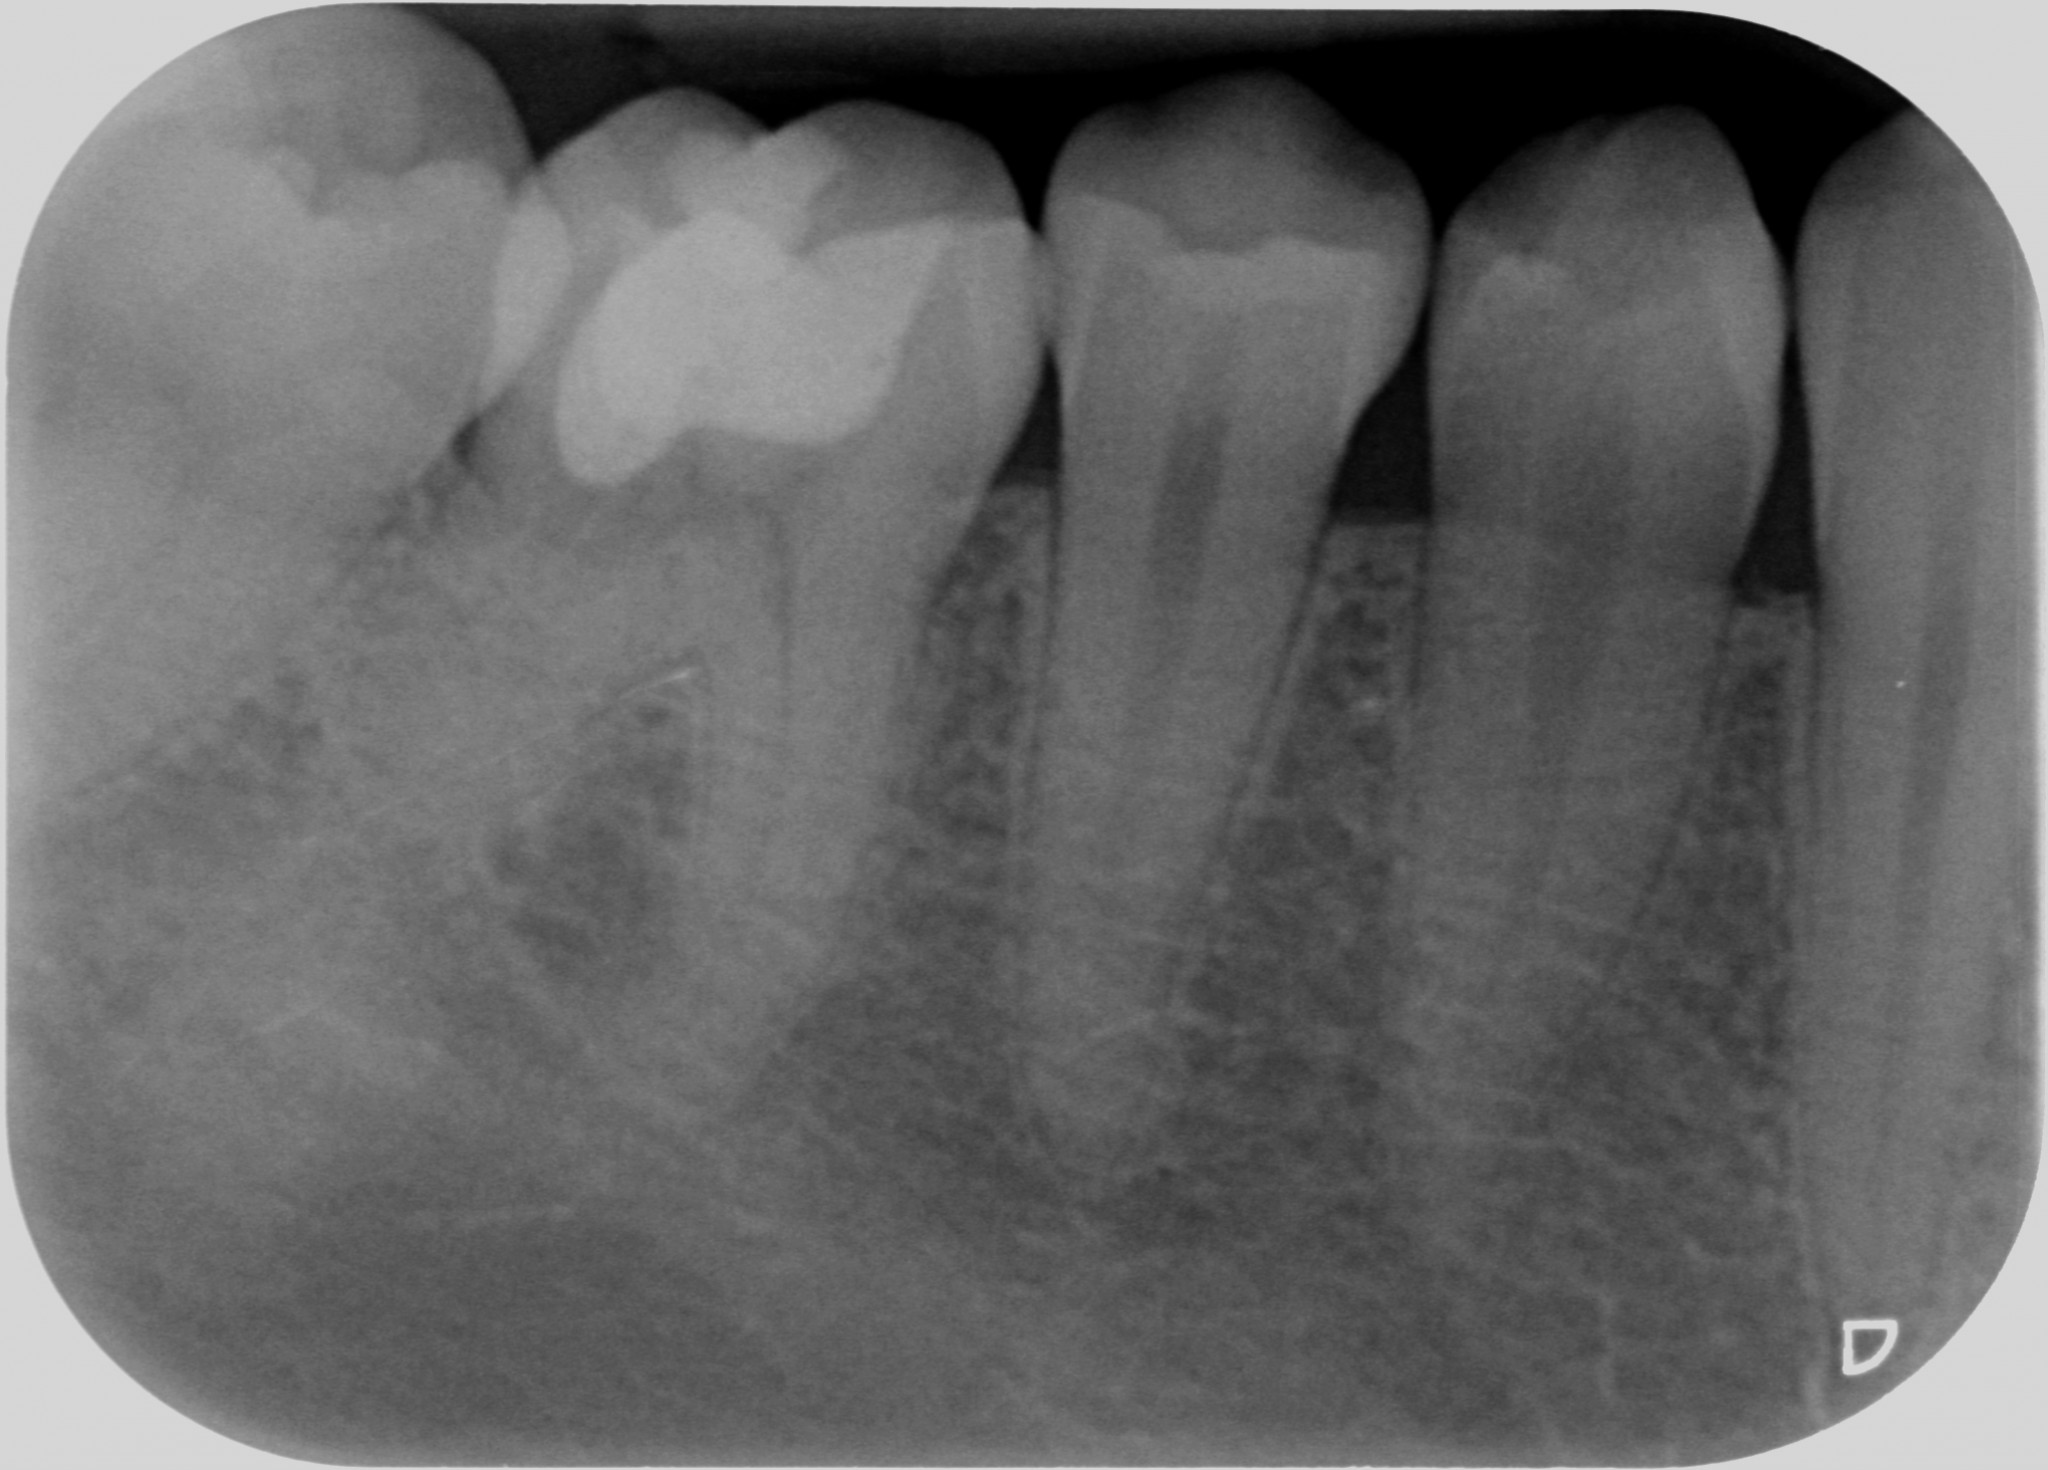

Dopo 5 anni la ragazza ha ancora un dente asintomatico e la rx indica che il processo si è arrestato.

Questo perché involontariamente avevo messo in atto una terapia corretta ad un problema che non conoscevo. Avevo rimosso nel miglior modo possibile fin dove potevo il tessuto di granulazione arrestando o rallentando il processo di distruzione del dente.

Quando nel 2013 mi è arrivato all’attenzione questo caso

Ho riconosciuto lo stesso fenomeno visto nella ragazza infestata da tessuti alieni di cui sopra e mi sono ricordato che all’università si era parlato di riassorbimenti esterni.

Allora ho studiato il fenomeno e ho saputo fare una diagnosi.

Si trattava di un riassorbimento esterno di classe IV.